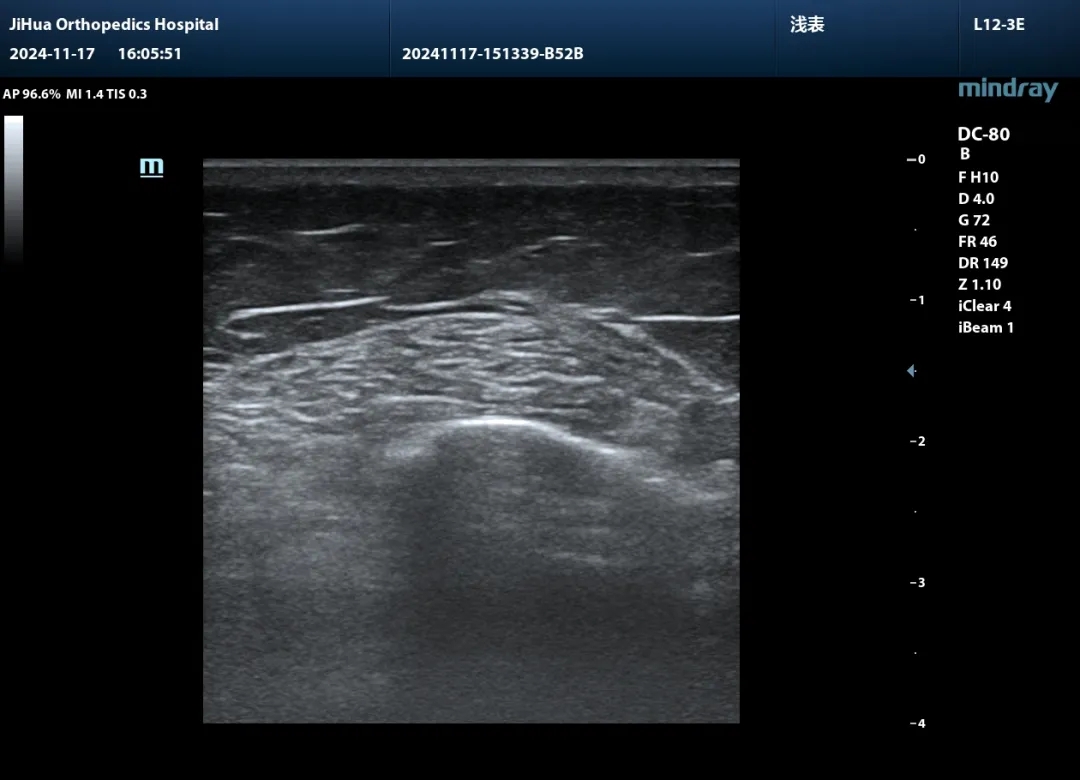

一旦體格檢查發(fā)現(xiàn)異常,現(xiàn)場(chǎng)即可啟動(dòng)影像掃查,清晰呈現(xiàn)損傷程度、失穩(wěn)根源與結(jié)構(gòu)障礙。結(jié)合X線、CT、MRI等影像資料,精準(zhǔn)的診斷思路豁然開(kāi)朗。